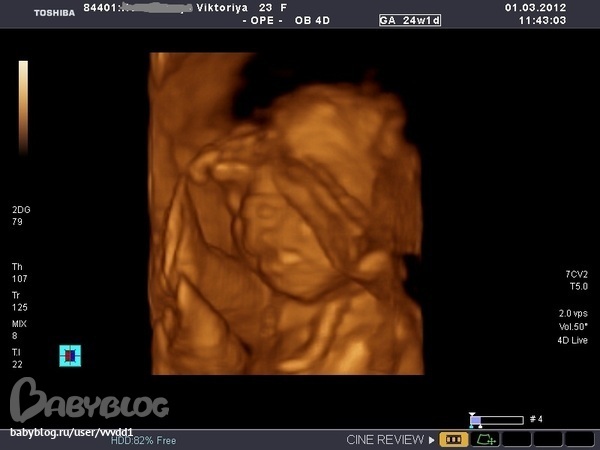

Результаты: УЗИ, КТГ, доплера, скринингаОчень понравилось,столько эмоций))))Пока мы ехали в больницу я слопала сникерс и уже в пути я начала ощущать пиночки.На узи нам подтвердили,что девочка.Малышка наша такая скромница, ручками глазки закрывала,пальчик сосет, а потом как дала боксом заниматься.Записали на диск видео, дали кучу фоток.Папа наш сидел,все налюбоваться не мог, говорит что она так на меня похожа.Весит наша принцесса 650 г.Врач очень хороший,много рассказывал,плацента поднялась,никаких аномалий развития не выявлено,Боже,как я попереживала за эту плаценту,как я рада,что все обошлось,а вот собственно и фотки нашего счастья